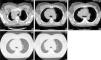

Continúa tratamiento y seguimiento ambulatorio por oncología, con sesiones de quimioterapia. Se observa cierta mejoría, tanto clínica como radiológica en las radiografías de tórax posteriores: reducción significativa de la masa paramediastínica del LSD (fig. 4).